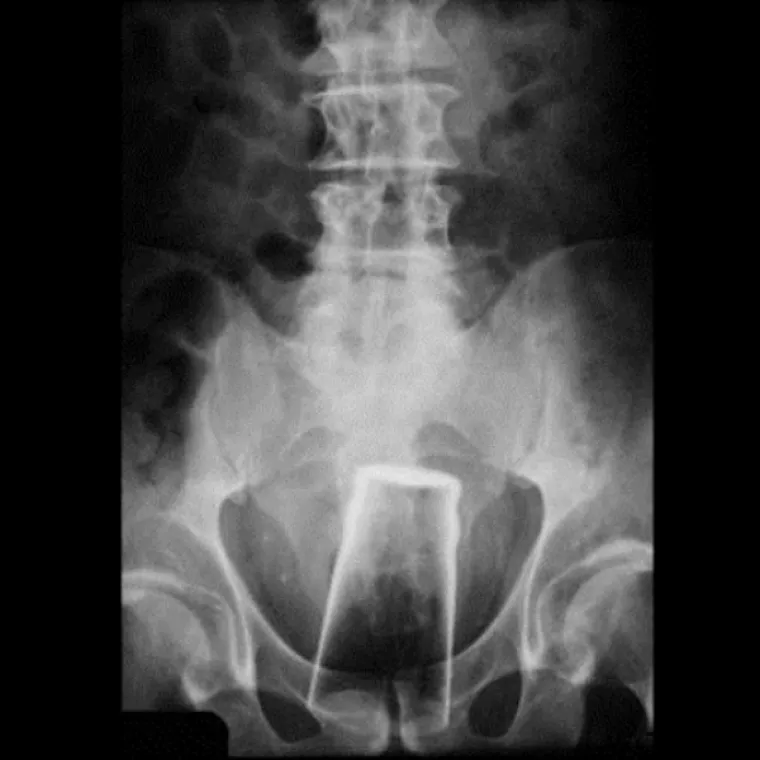

Čaša.